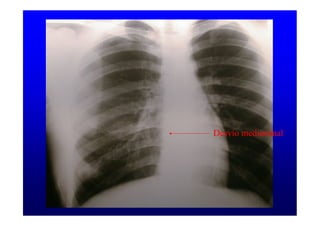

Desvío mediastinal